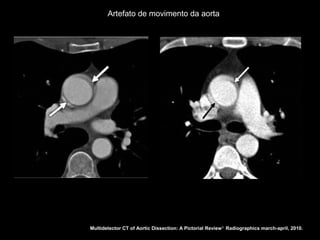

Artefato de movimento da aorta

Multidetector CT of Aortic Dissection: A Pictorial Review 1. Radiographics march-april, 2010.

Dissecção aórtica Tratamento: Stanford A: cirúrgico O acometimento da aorta ascendente ocorre em 50-75% das dissecções; Complicações fatais relacionados à extensão da dissecção às coronárias, valva aórtica, pericárdio ou pleura; Artefatos de movimento na raiz da aorta; Fase adicional curta com gating cardíaco.

Artefato de movimentoda aorta Multidetector CT of Aortic Dissection: A Pictorial Review 1. Radiographics march-april, 2010.

Artefatos de movimento na raiz da aorta;

Fase adicional curta com gating cardíaco.